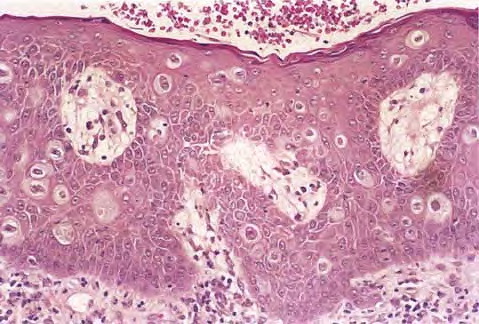

Pagetoid squamous cell carcinoma in situ =الورم شائك الخلايا من الدرجة صفر الباجيتوئيدي